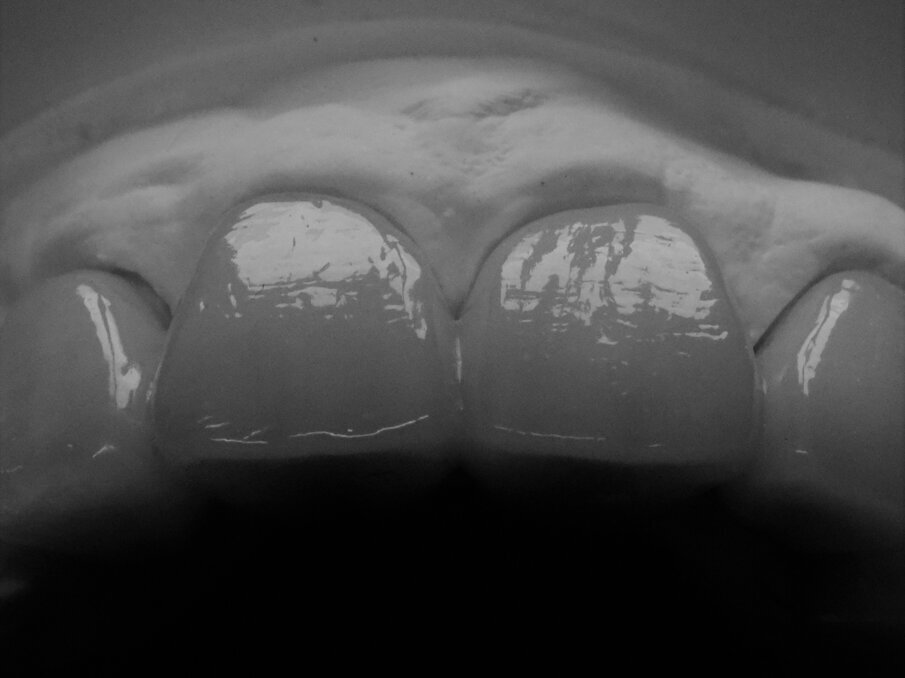

Tutti i margini di restauro vengono lavorati sotto lo stereomicroscopio per ottenere un risultato di precisione al fine di creare un restauro che mantenga la sua estetica e la funzionalità a lungo termine. Durante l’adattamento le impiallacciature vengono montate utilizzando una pasta rossa sulla matrice, trovando i punti di contatto adeguati sulla superficie di intaglio. Ciò consente una posizione più stabile delle faccette una volta posizionate in bocca. Inoltre, la precisione marginale e la stabilizzazione dell’impiallacciatura consentono al medico di trovare rapidamente la corretta posizione del restauro in bocca senza inclinarlo (Figg. 24-26).

Fig. 24 - Precisione marginale dell’impiallacciatura fissata sulla matrice master.

Figg. 25, 26 - Precisione marginale in bocca.